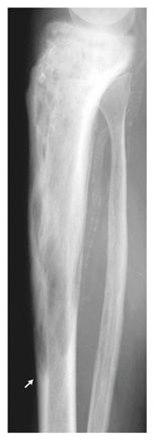

Sykdomsforandringer, lesjoner, kan finnes på ett sted eller flere steder i skjelettet. Tilstandén utvikler seg over tre faser. Første fase er økt nebryting av beinvev (økt osteoklastaktivitet), på røntgen ses det som mørkere flekker, lytiske lesjoner. I neste fase repareres dette med økt oppbygging av nytt beinvev, men dette beinvevet er mer uordnet enn normalt beinvev og det er mekanisk svakere. I siste fase forkalkes lesjonene, de beskrives som sklerotiske og fremstår som lysere på røntgen.

De knoklene hvor man hyppigst finner disse forandringene er leggbeinet (tibia), lårbeinet (femur), bekkenet (pelvis), ryggsøylen eller kraniet.